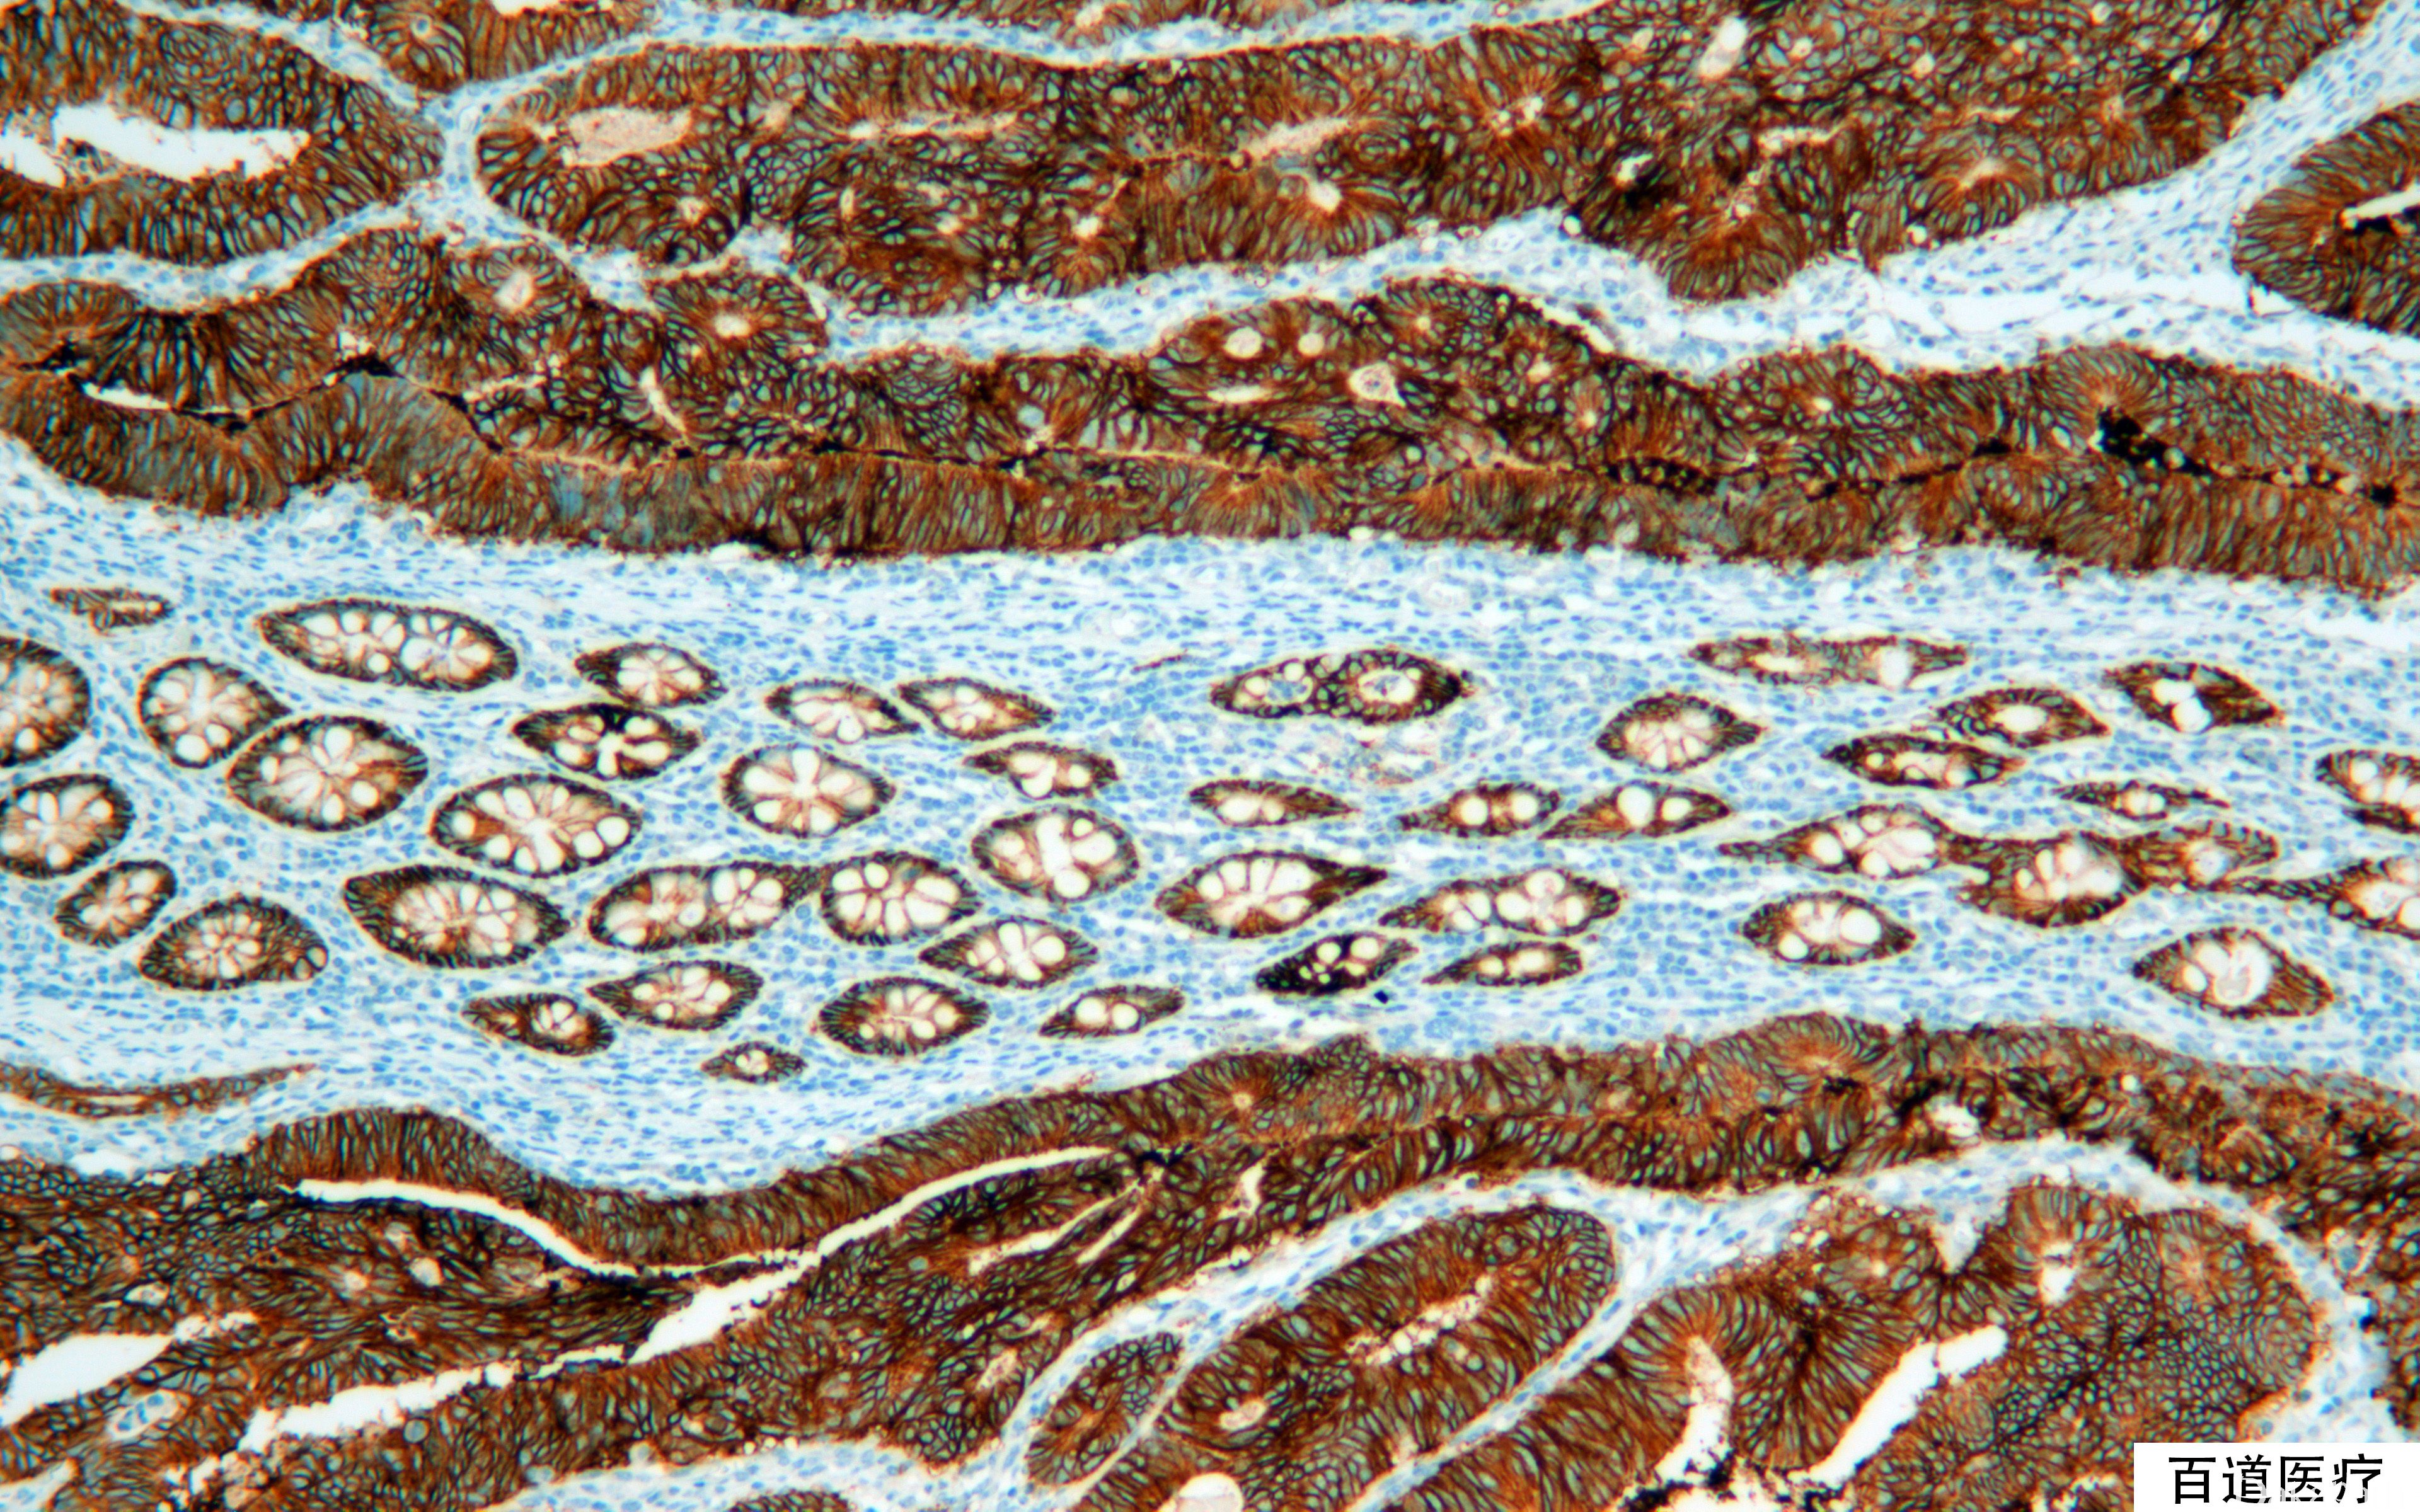

EpCAM

信号定位: 胞质、胞膜

几乎全部阳性(≥95%的病例阳性): 结直肠腺癌、前列腺腺泡性癌、皮肤基底细胞癌、类癌、甲状腺滤泡性腺瘤、甲状腺滤泡性癌、甲状腺乳头状癌、淋巴上皮癌、肺大细胞癌、涎腺腺泡细胞癌、黏液表皮样癌、卵巢无性细胞瘤、卵巢黏液性癌、外阴基底细胞癌、食管腺癌、甲状旁腺腺瘤、嗅神经母细胞瘤、子宫内膜腺癌、乳腺伴大汗腺分化的癌、甲状腺腺瘤、腹膜原发性腺癌、小肠腺癌、肝内胆管细胞癌、宫颈腺癌,非特指型、卵巢浆液性癌、甲状旁腺癌、胃肝样腺癌